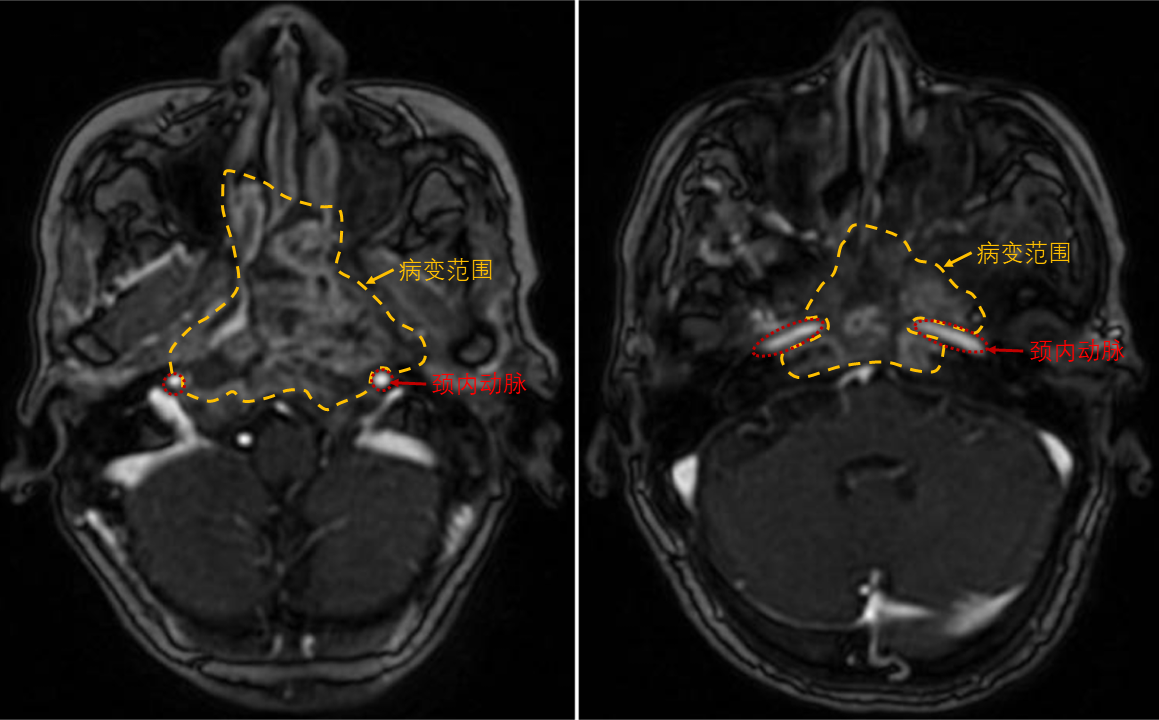

经人介绍,他们来到南华大学附属第一医院耳鼻咽喉科,找到刘志锋副主任医师。经过鼻颅底增强磁共振检查,发现病情确实极为棘手:肿瘤累计双侧鼻咽、颅底及毗邻的颈内动脉,左侧肿瘤较前明显增大,右侧伴有严重软组织及骨坏死。然而,刘志锋副主任医师团队经过反复研判,认为通过精密手术仍有一线切除希望。

双侧鼻咽部病变范围累及颈内动脉

为确保安全,科室迅速组织了多学科(MDT)会诊。术前关键的左侧颈内动脉球囊闭塞试验(BOT)结果呈阳性,这如同一道“红色警报”,意味着术中若该侧颈内动脉发生意外损伤或必须被阻断,患者极可能发生灾难性的脑缺血事件,风险陡增。因此,手术的终极挑战在于:必须在不损伤双侧颈内动脉的前提下,彻底切除所有病变组织。这对主刀医生的技术、耐力与心理素质提出了极限要求。